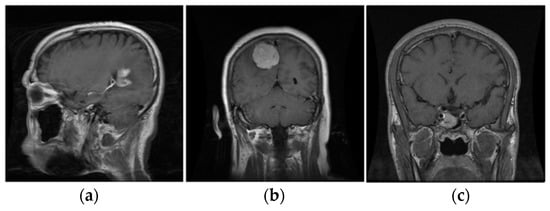

Figure 4.

The three types of tumors. (a) Glioma; (b) Meningioma; (c) Pituitary.

The enhanced resultant images were resized and concatenated three times, as per the standard input image size of the pre-trained DL models, to create channels. All three variants of ResNet: ResNet18, ResNet50, and ResNet101, the best-performing pre-trained DL models [10] for brain tumor classification, have a standard input image size of .